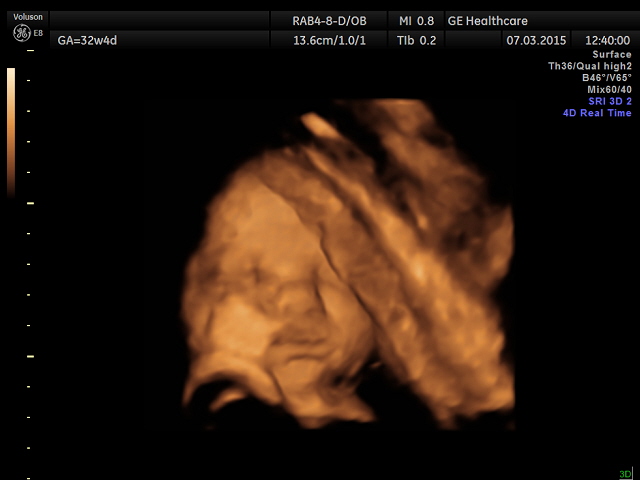

Наши будни, наши неделькиВот и мы решили показаться :) нам уже 32.4

все хорошо, продолжаем ходить дальше!

Красавица! Дочка прям хорошо вышла на 3Д, нас долго узист ловил, чтоб фото сделать)